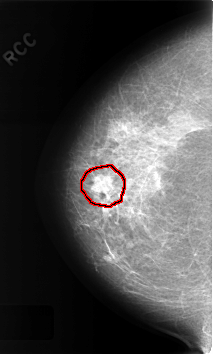

C_0338_1.RIGHT_CC

FILE: C_0338_1.RIGHT_CC.OVERLAY

TOTAL_ABNORMALITIES 1

ABNORMALITY 1

LESION_TYPE MASS SHAPE LOBULATED MARGINS CIRCUMSCRIBED

ASSESSMENT 4

SUBTLETY 5

PATHOLOGY BENIGN

TOTAL_OUTLINES 1

BOUNDARY